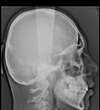

- Et aussi la réalisation de radios panoramiques et de téléradiographies de profil.